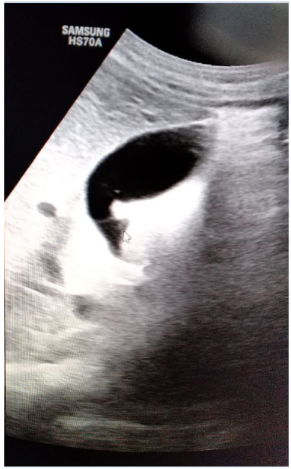

A 40-years-old non-smoker, non-alcoholic, vegetarian male presented with mild to moderate pain in right upper abdomen for 4 to 5 months. Pain was aggravated after the meal. There was history of two episodes of vomiting after attack of severe pain in last one month. He consulted to his family physician for the same complaints and took antacids and proton pump inhibitors (PPIs) but got only time being relief. Ultrasonography (USG) abdomen Figures 1 & 2 showed well distended gallbladder with normal wall thickness but sludge in the lumen. The patient was advised for the laparoscopic cholecystectomy and for the same referred to us. The patient was then thoroughly examined and nothing significant could be detected in systemic or local examination. The blood biochemistry and serology were also within normal limit except raised Aspartate transaminase (AST) 89 IU/L and Alanine aminotransferase (ALT) 142 IU/L. Patient was given OmlivTM, one tablet twice daily for 45 days. The follow-up USG (Figure 3) revealed normally distended gallbladder with normal wall thickness and clear lumen. It was concluded that the OmlivTM can clear the gallbladder sludge and is also effective for the symptomatic improvement of the patient.

Figure 3 Case No. 1 [Post-treatment ultrasonography scan showing clear gallbladder lumen].